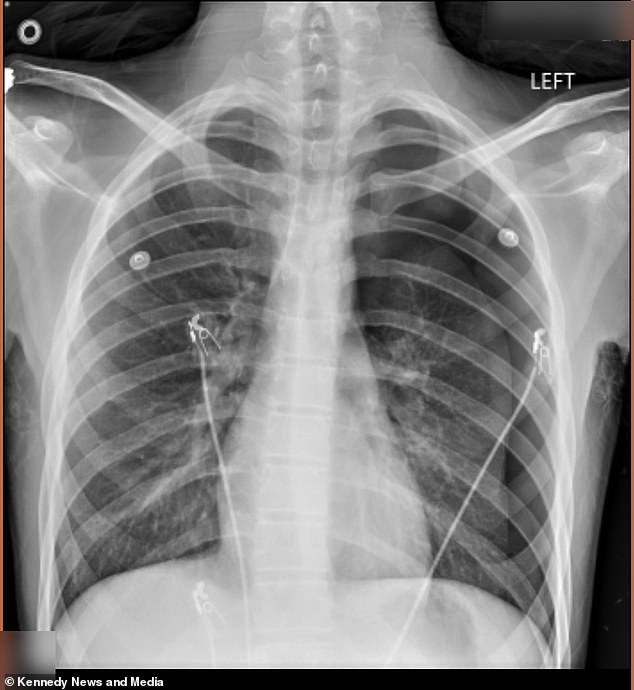

A Kentucky mother is speaking out in a desperate bid to warn other parents about the dangers of vaping, after her 17-year-old son suffered two collapsed lungs from the habit. Cameron Vann, known to friends as 'Dodge,' began vaping two years ago to 'look cool' at school, a decision he kept hidden from his mother, Crystal Vann. The secret came to light in September 2025, when Dodge emerged from the school bus pale and in severe back pain. His mother rushed him to the emergency room, where a chest x-ray revealed a pneumothorax—a collapsed lung—with 50 percent of his left lung affected. Doctors had to insert an 18-inch tube into his chest to remove the excess air and allow his lung to re-expand. Despite the surgery, Dodge continued vaping in secret, unaware of the risks he was taking.

The second collapse came in January 2026, when Dodge called his mother in excruciating pain, unsure whether his symptoms were related to his lungs. This time, doctors warned that he could have died in the hospital lobby. The second surgery was more severe: a pleurodesis, where doctors scraped the lining of his lung and stapled air-filled blisters called blebs to the top of his lung. They then reattached the lung to the chest wall. 'He went through a lot,' Vann said. 'I thought, "Why him?" I feared he was going to die.' Her son's friends had tried vaping first, but Dodge followed suit, a decision he now regrets deeply.